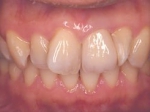

術前口腔内(正面観)

インセラム(オールセラミック)冠による修復。 主訴は前歯が汚い 金属を使わないオールセラミックでの治療を勧めた。 術前